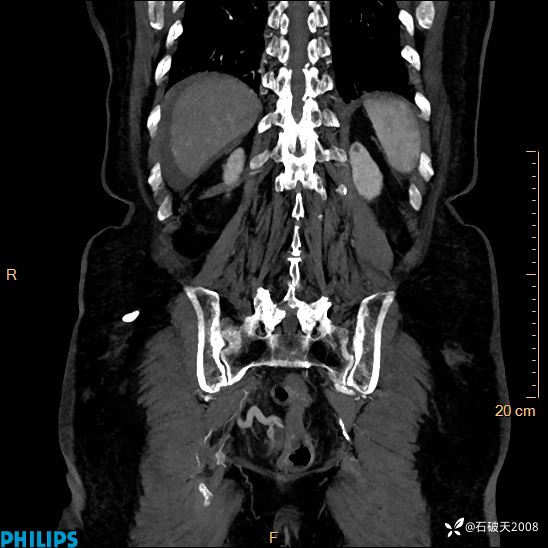

女82岁 主 诉:腹痛半月,加重3天

现病史:半月前患者无明显诱因出现腹痛,上腹部、下腹部间断隐痛,进食后明显,腹胀,大便干,无反酸、烧心,无恶心、呕吐,无腹泻、发热,无咳嗽、咳痰,无心慌、胸闷、无头痛、头晕,无粘液脓血便等症状,患者就诊XXXX医院,给予中草药治疗(具体药物不详)治疗,效差,3天前患者腹痛较前加重,上腹部、下腹部间断隐痛,伴间断性绞痛,今为求进一步诊治来诊我院,门诊以“腹痛”为诊断收住院,自发病来神志清,精神差,饮食差,睡眠一般,小便正常,体重无明显变化。

动脉期